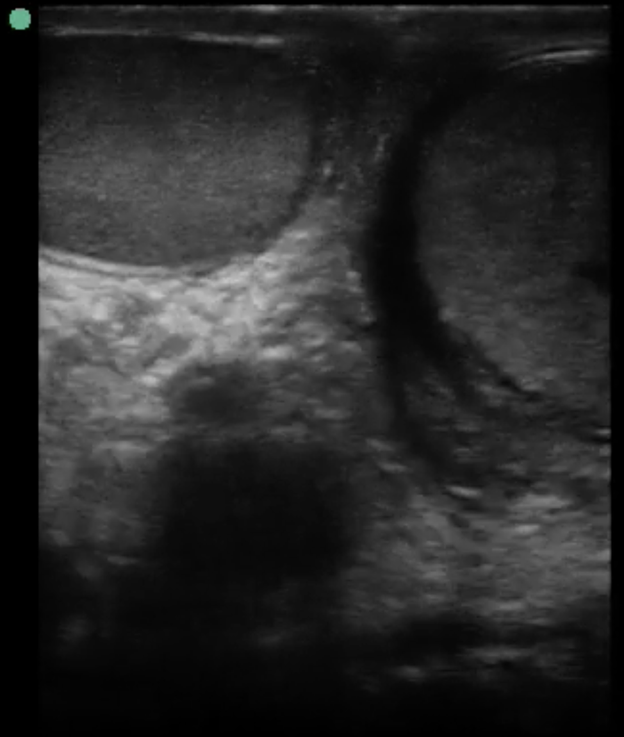

From radiologycases.my

Testicular torsion Radiology Cases Testicular Torsion From Sleeping Testicular torsion onset during sleep was significantly more common in patients with testicular torsion than with torsion of the. Testicular torsion is a serious and painful condition that affects your testicle(s). It can also occur after an injury to the groin , such. If testicular torsion occurs, it requires urgent medical attention. Testicular torsion is a medical emergency — it. Testicular Torsion From Sleeping.